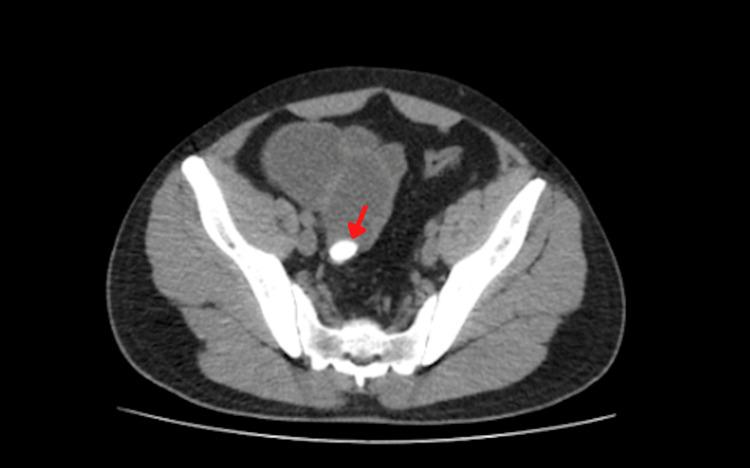

Gallstone ileus is a rare presentation of gallbladder disease. It is mostly encountered in female and elderly patients. It occurs when a stone causes a fistula between the gallbladder and the intestinal lumen. More than half of the patients do not have a history of biliary disease. Surgical intervention is still considered the best treatment option; however, the best choice between one-stage and two-stage surgery is still unknown. We present a gallstone Ileus case in a patient with uncommon epidemiological characteristics: a 28-year-old male Hispanic patient without a gallbladder disease history.

胆结石性肠梗阻是胆囊疾病的一种罕见表现。多见于女性和老年患者。当结石导致胆囊与肠腔之间形成瘘管时就会发生。超过半数的患者没有胆道疾病史。手术干预仍然被认为是最佳治疗选择;然而,一期手术和二期手术之间的最佳选择仍不明确。我们报告一例具有不寻常流行病学特征的胆结石性肠梗阻病例:一名28岁无胆囊疾病史的西班牙裔男性患者。